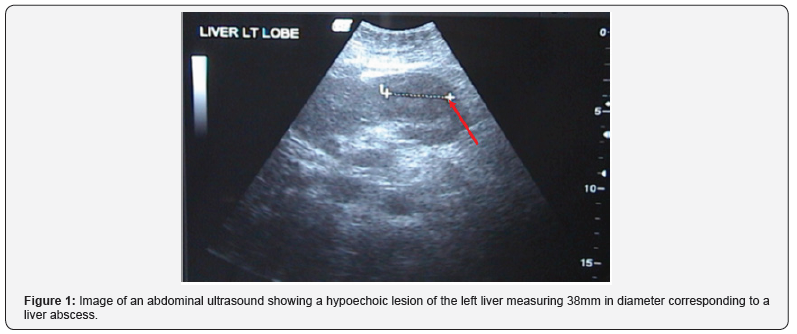

Clinically, she presented with fever (38C), jaundice and tenderness upon palpation of the right upper quadrant. Laboratory exams showed alteration of her liver function tests: bilirubin total / bilirubin direct = 6.6/3.9mg/dl (normal <1.5/<0.5), Gamma GT = 377U/l (normal < 80), Alkaline phosphatase = 271U/l (normal <140). Serologies for hepatitis B and C were negative. Abdominal ultrasound was done and showed a hypoechoic lesion of the left liver measuring at 38mm that correspond to a liver abscess (Figure 1); no dilation of the intra and extra hepatic biliary tree was present. A magnetic resonance cholangiopancreatography (MRCP) revealed an irregular 2cm biliary tree stenosis located at the common hepatic duct and another stenosis located at the left hepatic branch (Figure 2). A circular 4cm lesion was located at the level of segment II and segment III that may correspond to a liver abscess associated with multiple micro abscesses (Figure 3).